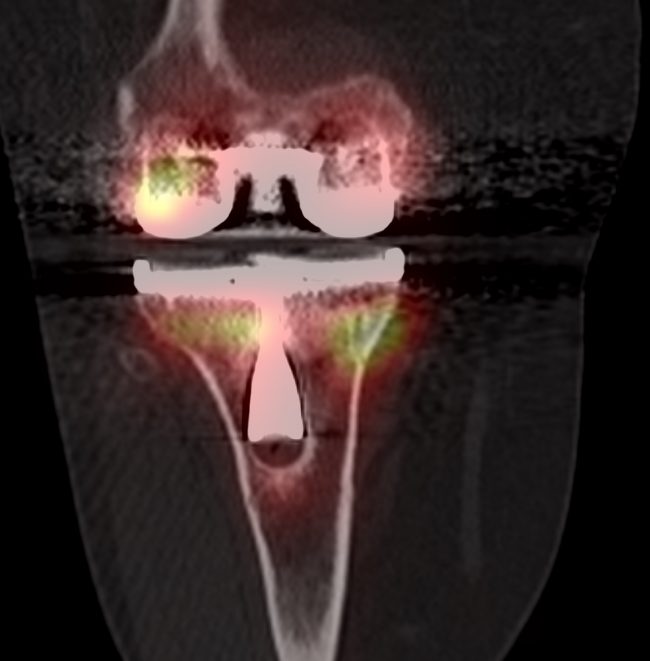

Clinical presentation 50 year old woman with a chronic history of pain in the lower back. A bone SPECT-CT of the lumbar spine was performed. Key Findings Lumbosacral transitional vertebra (LSTV) with fused right transverse process of L5 with the sacrum. Low grade uptake in the Castellvi 2a LSTV. Intense increased uptake in the left…